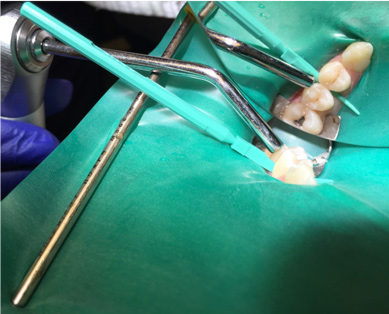

4. Remove the separator. If needed to accommodate the applicator, utilize one of the wedges provided in the proximal resin infiltration kit to create more space between the teeth (Figure 4).

Fig 4. A wedge is used if more separation is required.

Figure 4

Fig 5. The proximal applicator is inserted with an etch.

Figure 5